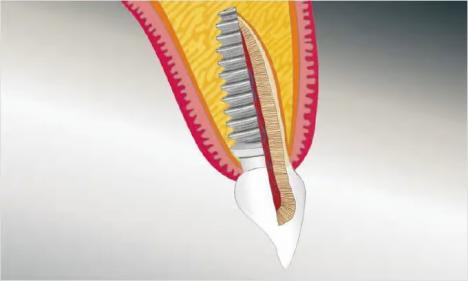

Für ein Implantat werden sowohl eine Mindestknochentiefe als auch ein Sicherheitsabstand im Unterkiefer zum Nervenkanal vorausgesetzt. Die Knochentiefe wird durch spezielle Röntgendiagnostik ermittelt.

Die reale Knochenhöhe wird mit Hilfe einer Röntgenschablone ermittelt. Bei unserem digitalen Röntgengerät kann gegebenenfalls auf die Messschablone in Einzelfällen verzichtet werden, da es über ein integriertes Messtool verfügt. Zur Detailabklärung kann es erforderlich sein, zusätzliche Aufnahmen von einzelnen Zahnabschnitten zu machen.

Durch die digitale Volumentomographie (DVT) kann die Lage der später zu setzenden Implantate im Vorfeld schon auf den Millimeter bestimmt werden, dies ist nur in Einzelfällen notwendig.

Panorama-Röntgenaufnahme - Implantat im Oberkiefer